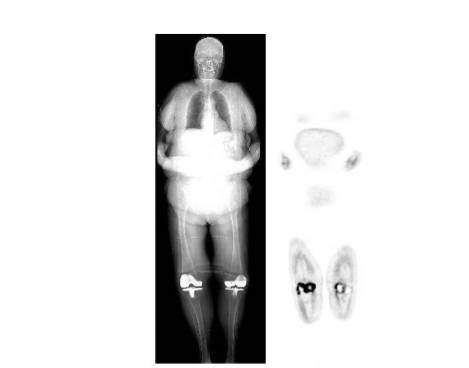

Imaging is performed one-two hours after radiopharmaceutical administration. The normal distribution of ¹⁸F-FDG includes the brain, myocardium, and urinary tract. Thymic uptake is sometimes seen, especially in children. Gastric and bowel activity are variable. Liver, spleen and bone marrow uptake generally are low-grade (Figure 10)³³.

Figure 10.

Normal ¹⁸F-FDG maximum intensity projection image. There is brain, myocardial, urinary tract, and colonic activity. Faint bone marrow activity also is present.